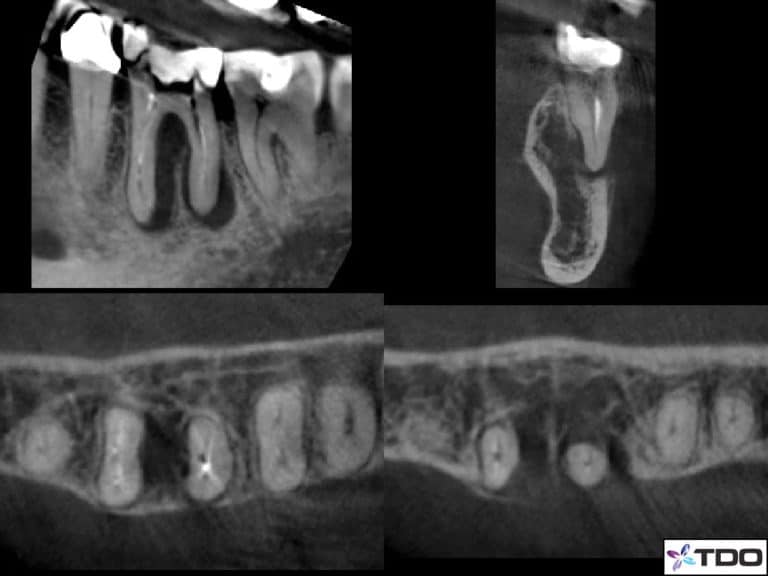

J Lesion Dental . This is not a cracked tooth despite the radiographic presentation. This chapter is designed to simplify the process of arriving at a. However upon closer review, there is definitive spicule of bone attached to the distal cej. a vertical root fracture (vrf) is a common and often devastating event. When identified, the treatment plan is straightforward: This description of a lesion is what has made so many practitioners believe that a vertical root fracture is a super hard diagnosis. specifically, when the bone loss presents in “j” shaped pattern, it is highly suggestive that a root fracture is present. differential diagnosis of radiolucent lesions of the jaws. The shape may be due to the radiographic.

Does a JShaped Lesion Always Mean Extraction? J Lesion Dental The shape may be due to the radiographic. a vertical root fracture (vrf) is a common and often devastating event. specifically, when the bone loss presents in “j” shaped pattern, it is highly suggestive that a root fracture is present. When identified, the treatment plan is straightforward: This description of a lesion is what has made so many. J Lesion Dental.

Lower second molar with “J” shape lesion MyZerodonto J Lesion Dental When identified, the treatment plan is straightforward: This chapter is designed to simplify the process of arriving at a. specifically, when the bone loss presents in “j” shaped pattern, it is highly suggestive that a root fracture is present. differential diagnosis of radiolucent lesions of the jaws. a vertical root fracture (vrf) is a common and often. J Lesion Dental.